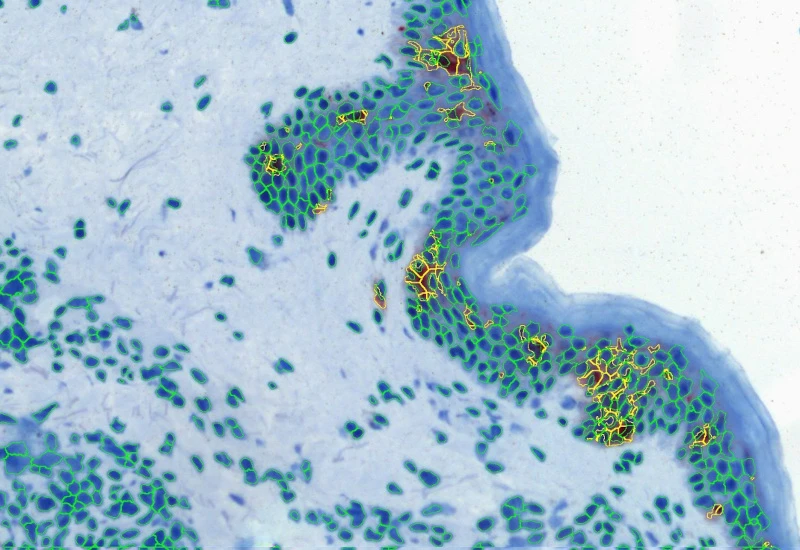

The IHC Macrophages App detects macrophages based on adequately stained IHC samples (e.g. CD68). The App further proves area detection and distance range algorithms to determine the distance of Langerhans cells from the border of the epidermis within and without. Each segmented cell compartment is measured for up to 20 parameters, as is the distance of each cell to the boundary.

Original image

Nuclei and marker detection